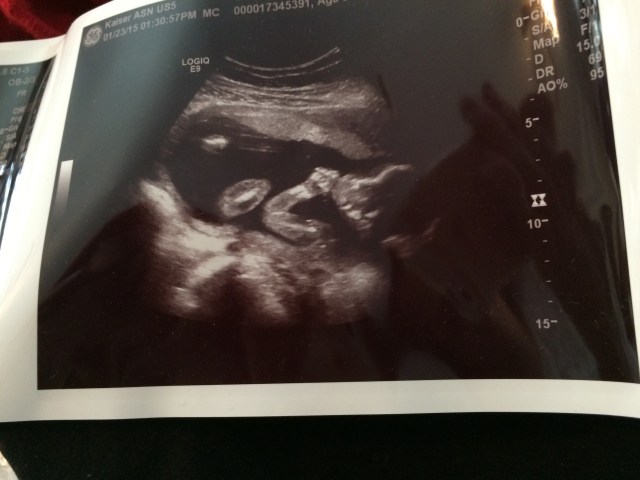

I can’t believe it, but we made it to the halfway mark. Three more weeks to the “viability” date, and of course, a goal of twenty more weeks and a full-term guy. (39 weeks says March of Dimes)

I had an appointment this week wherein we discussed my headaches (maybe get a massage?), numbness in my hands (should peak at 28 weeks–so this could get worse?!?!), and my other small concerns; it seems they all come with the territory. I am developing something called SPD, which is a painful stretching of the hips in opposition. I got a sort of brace, and I tough it out. I’m still very sensitive to smells–today I gave my mom 80% of my scented products as I can no longer smell most of them without gagging. I’m tired, my feet hurt, but I can deal with all of that!